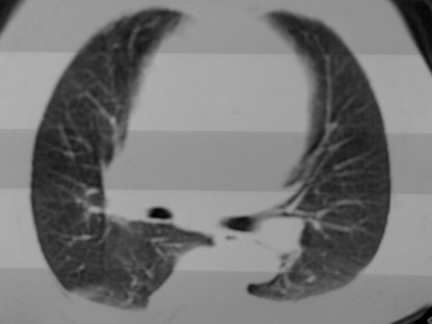

标题: CT13142:女 80 胸闷、气短、1w [打印本页]

标题: CT13142:女 80 胸闷、气短、1w

右肺炎性变

双侧胸腔积液

右肺感染;双侧胸腔少量积液,心影增大,可能与心功不全有关;胸内甲状腺肿。

胸内甲状腺肿;右肺感染;双侧胸腔少量积液。